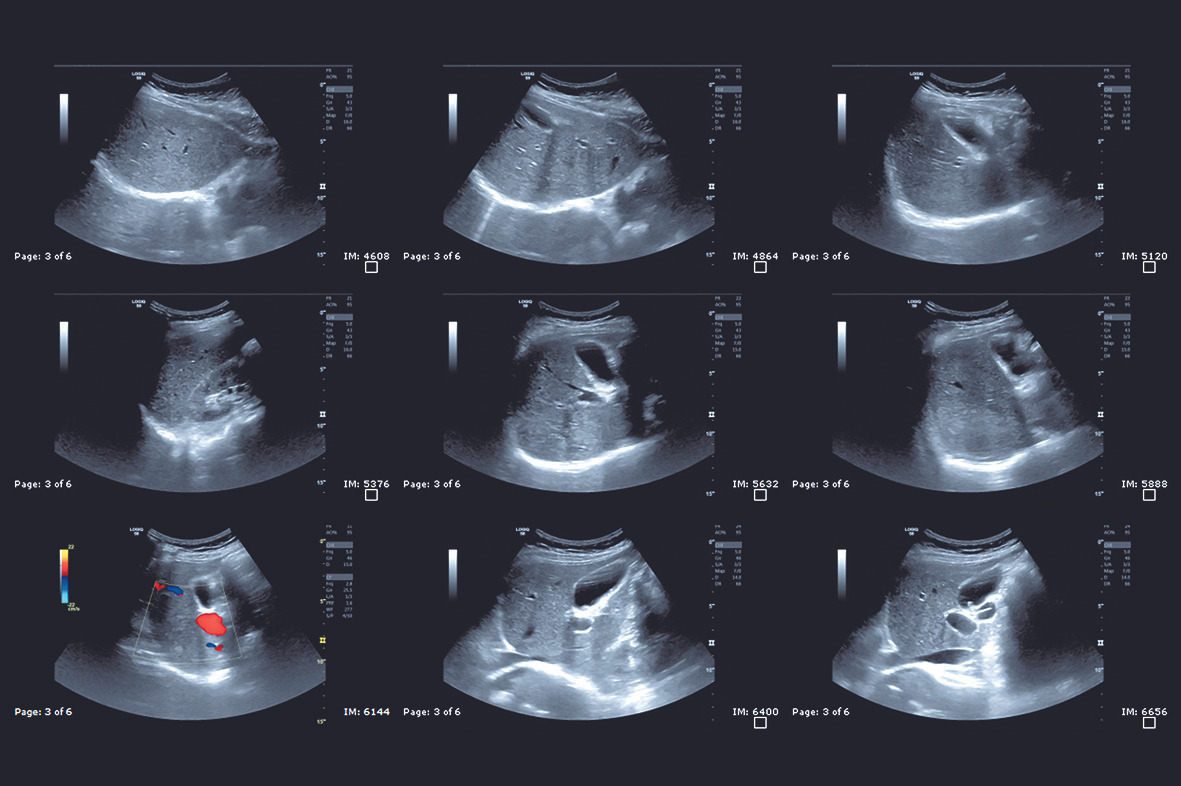

복부 초음파는 초음파를 이용해 인체 내부 장기의 구조를 실시간으로 영상화하는 검사입니다. 검사 시 피부에 젤을 바르고 탐촉자를 이용해 복부를 스캔하며, 장기 크기, 모양, 내부 조직 상태 등을 확인합니다. 특히 간과 담낭, 췌장, 비장, 신장 등 고형 장기의 평가에 매우 효과적입니다. 통증이 없고 검사 시간이 10~20분 정도로 짧은 것이 특징이며, 반복 검사에도 부담이 적다는 장점이 있습니다.

복부 초음파 검사는 비교적 간단하면서도 다양한 장기 상태를 확인할 수 있는 대표적인 영상 진단 방법입니다. 방사선 노출이 없고 검사 시간이 짧아 건강검진이나 증상 평가에서 매우 널리 활용됩니다. 특히 간, 담낭, 췌장, 신장 등 주요 장기의 이상 여부를 빠르게 파악할 수 있어 초기 질환 발견에 유리한 검사로 평가됩니다. 최근에는 건강검진 항목으로도 많이 포함되면서 관심이 높아지고 있으며, 비용과 검사 주기에 대한 문의도 증가하는 추세입니다.